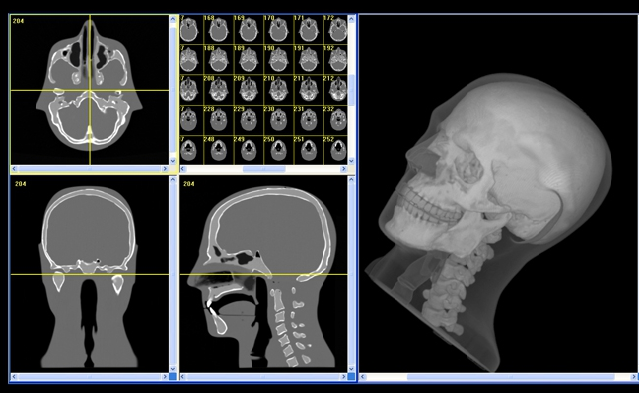

711型牙科診斷用頭模是頭部診斷放射學(xué)的參考標(biāo)準(zhǔn)。模型旨在幫助工程技術(shù)人員和臨床醫(yī)師練習(xí)如何選擇大多數(shù)放射學(xué)程序中常見的掃描參數(shù),并攝片求證是否可以獲得所需的精準(zhǔn)的解剖圖像細(xì)節(jié)。

頭模為研發(fā)人員,臨床醫(yī)師和工程技術(shù)人員在牙科X射線,全景X射線,CT和錐束CT程序培訓(xùn)方面提供了可靠的工具。它是確定系統(tǒng)設(shè)置,調(diào)試新設(shè)備,監(jiān)測(cè)系統(tǒng)性能的理想選擇。

模型包括一個(gè)用于定位在錐形束CT或全景X射線系統(tǒng)內(nèi)的可調(diào)支架。 體模的顎部略微打開,前牙垂直對(duì)齊(接近有一個(gè)咬合導(dǎo)板)的位置,以便牙科掃描系統(tǒng)可以重復(fù)正確定位。 請(qǐng)注意,本產(chǎn)品無法放置實(shí)際的咬合板。

模型由專有的組織等效材料構(gòu)成,模擬人體組織在CT和(50keV-25MeV)治療能量范圍的X射線衰減特性。 體積和結(jié)構(gòu)近似于男性平均頭部。 模型具有詳細(xì)的三維擬人解剖學(xué),包括腦,骨,喉,氣管,竇,鼻腔和牙齒。 骨骼包含皮質(zhì)層和骨小梁部分。 牙齒包括不同的牙質(zhì),牙釉質(zhì)和帶有神經(jīng)的根結(jié)構(gòu)。 竇腔完全打開。

適用于牙科錐束CT和全景X射線的真實(shí)的頜面模型